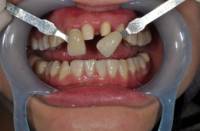

☞准备工具:单反相机、环形闪光灯、微距镜头85mm以上、张口器、黑色板、反光板、比色板

干货集结:

快门 1/125 、 光圈 F25 、 ISO 100

拍摄主体面向光源,不可多反光

比色板与牙齿保持于同一水平线